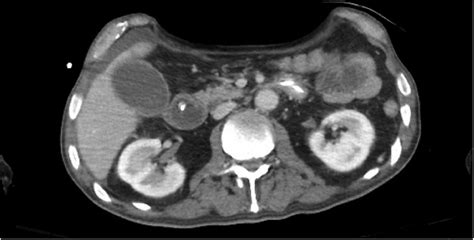

• Imaging Studies: X-rays, CT scans, or MRIs to visualize the abdominal area and identify any underlying issues.